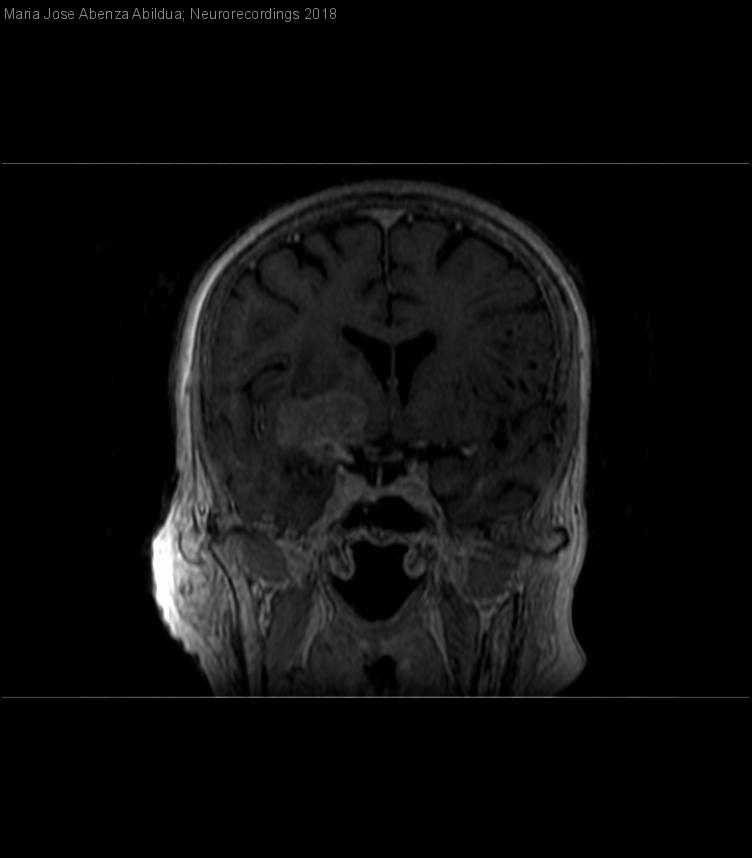

Meningitis carcinomatosa

Mujer | 70 años

Diagnóstico final: Carcinomatosis meningea

Estado actual: Mujer de 70 años, diagnóstico reciente de Leucemia linfática crónica vs linfoma linfocítico de célula pequeña estadio O/A, sin tratamiento. En estudio de extensión de observan LOES cerebrales....